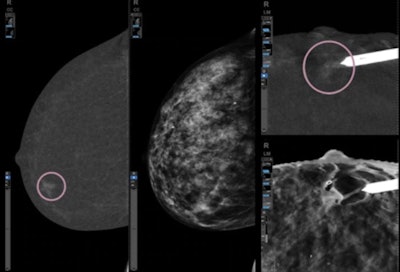

Serena Bright is a new contrast-enhanced guided biopsy technology that allows these exams to be performed on the same mammography equipment, rather than requiring patients to be transferred to a breast MRI scanner.

Serena Bright is based on the company's SenoBright HD contrast-enhanced spectral mammography (CESM) technology, which highlights unusual blood flow patterns and can be performed after an inconclusive mammogram or ultrasound exam. SenoBright HD is offered as an option on Pristina.